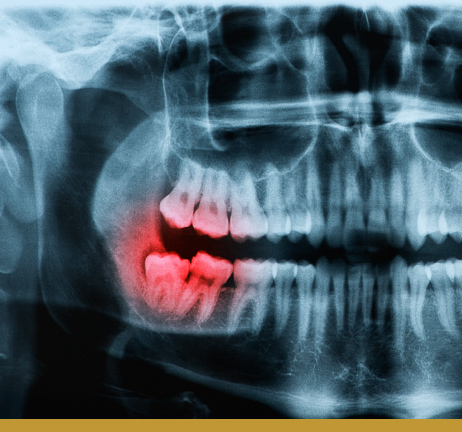

Wisdom teeth, or third molars, typically emerge between ages

17–25. When there isn’t enough room in the mouth, they can

become impacted, cause crowding, infection, or even damage

nearby teeth.

Imaging helps us evaluate tooth position, angle, and bone structure